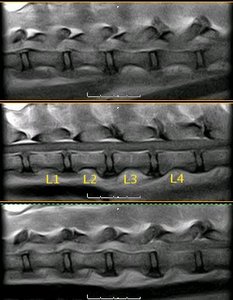

Radiografía laterolateral de la columna vertebral lumbar canina |

Radiografía laterolateral de la columna vertebral lumbar felina |